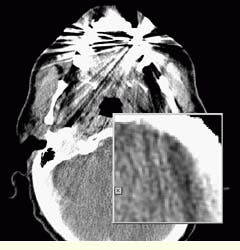

According to Dr. Jensen, the radiologist`s image-interpretation time varies depending on the case, type, and complexity of the incoming scan. For example, the total interpretation time from transmission to completion for a negative CT scan is on the order of five to six minutes. Jensen points out that although a standard CT scan of a patient`s head is generally made up of 13(15 CT slices and takes about three minutes to download completely over the ISDN/DICOM network, the radiologist can begin interpreting the images as soon as they are displayed.

According to Jensen, the Images-on-Call digitally transmitted imagery is comparable in quality to conventional film and offers other advantages to diagnosticians. "Unlike earlier image-transmission systems that didn`t transmit actual raw image data, now 75% of the images sent from the major centers come with DICOM interfaces that allow the examination of the images in all sorts of display formats."

For example, Jensen notes that a standard chest film given to a radiologist in a hospital does not provide useful information for specifically examining bones. To provide bone information, additional film must be prepared in a different "bone-window" format. On the other hand, "with the DICOM interfaces, we can just click on this configuration and examine bone images immediately."